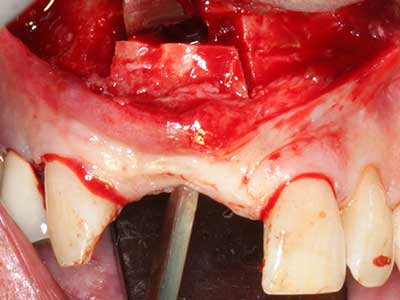

Aplicación: Partición ósea / Cortical Split

El tejido óseo no solo tiene un contenido puramente mineral, sino que también presenta una importante proporción de fibras de colágeno. Esto no solo garantiza una buena resistencia a la presión, sino también una cierta flexibilidad, que puede aprovecharse para la realización de aumentos. En la plastia de expansión clásica a efectos de una partición ósea, la cresta maxilar atrofiada se divide en su eje longitudinal y, tras alcanzar una profundidad de osteotomía suficiente, se extiende con cuidado (fig. 13-16), en un caso ideal sin desperiostizar de forma visible el maxilar (Brugnami, Caiazzo et al. 2014, Stricker, Fleiner et al. 2014). Los sistemas de tornillos y placas con distancia de expansión creciente han demostrado su eficacia para distanciar entre sí las dos tablas óseas por debajo del umbral de rotura. Por regla general, se requieren anchuras de hueso residual de al menos 3 a 4 mm (Chiapasco, Zaniboni et al. 2006) para garantizar una flexibilidad y una cobertura ósea suficientes de los implantes que van a incorporarse. En caso necesario, una osteotomía de descarga vertical unilateral o bilateral puede mejorar la flexibilidad. Como alternativa a la técnica clásica se ha descrito una combinación con otras técnicas de aumento, sobre todo en la parte bucal.

Con el uso de sierras piezoeléctricas la división se efectúa de forma especialmente cuidadosa y sin pérdidas importantes de las dimensiones, por lo que no se han encontrado diferencias significativas entre los implantes realizados en el maxilar dividido y en la cresta alveolar no deficitaria (Chiapasco, Zaniboni et al. 2006, Danza, Guidi et al. 2009). No obstante, precisamente en la partición profunda y limitada de forma local, es preciso asegurarse de que exista una adecuada irrigación por agua para evitar que se produzcan sobrecargas térmicas en las áreas de osteotomía apical.